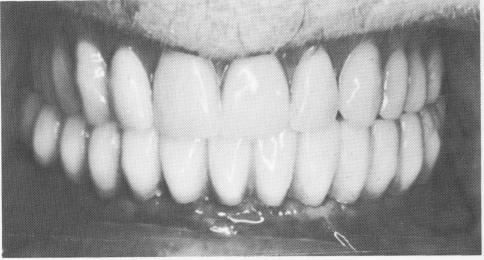

Fig. 13-31. A full arch fixed denture was cemented over the abutments.